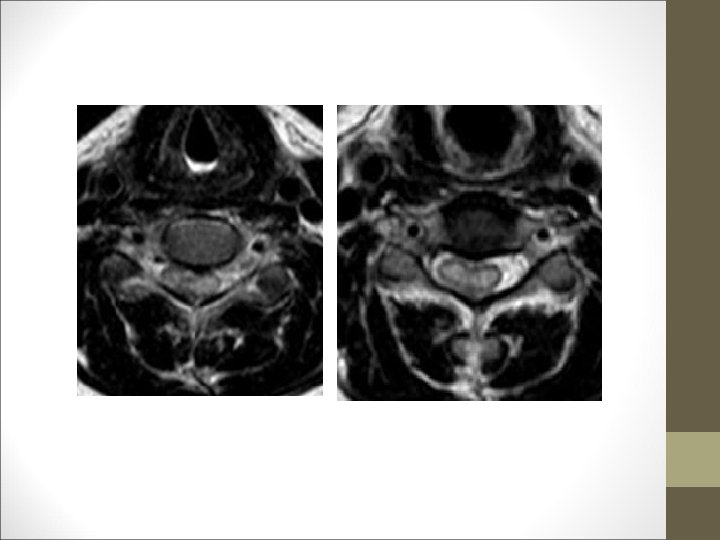

TC Desplazamientos de fragmentos óseos ¿Algo mas? Desplazamientos discales y lesiones ligamentosa FACULTAD DE MEDICINA DEPARTAMENTO DE CIRUGÍA NEUROCIRUGÍA RM

Cirugía Urgente ¿Creéis que se encuentra indicada? ¿Qué tipo de lesión medular teníamos? Incompleta ¿ Se redujo la subluxación? Cirugía urgente LESION MEDULAR INCOMPLETA • Progresión de los signos neurológicos • Hallazgo de fragmentos óseos o blandos q causen compresión. • Necesidad de descomprimir raíz espinal esencial • Subluxación irreductible • Hematomas ¿ Se redujo la subluxación? Sí, se redujo 2) Estabilización y Fijación en un 2º tiempo NO cirugía urgente